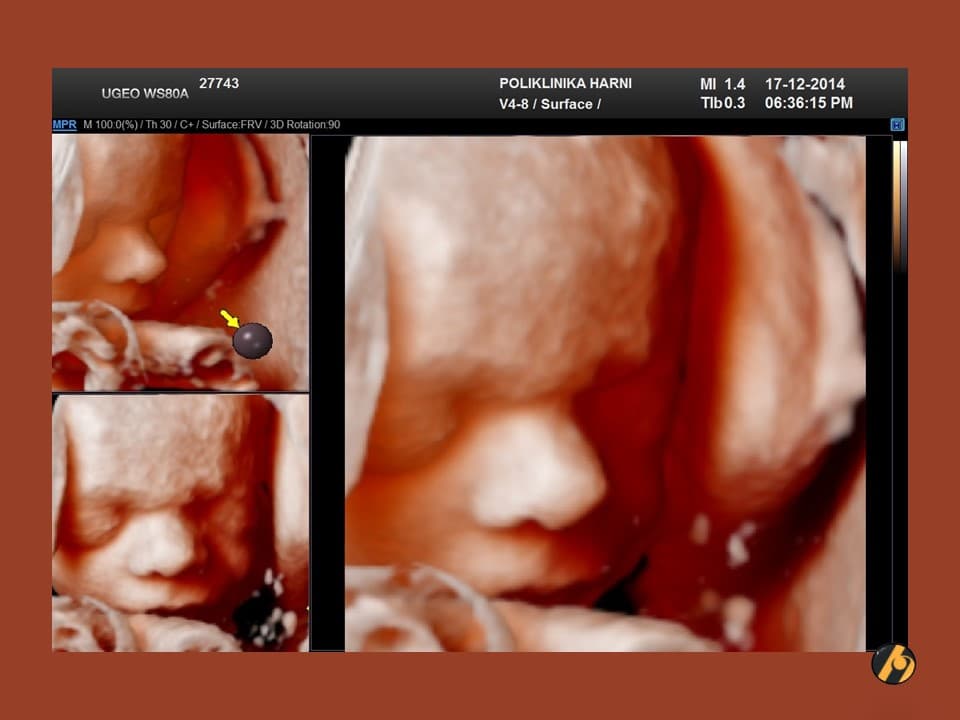

S 37. tjednom trudnoće Vaša beba postaje klinički zrela i potpuno spremna za porod. S ovim tjednom se također završava razdoblje mogućeg preranog poroda.

Vaša beba dugačka je oko 47 cm, i teška 2,750 – 2,950 g.